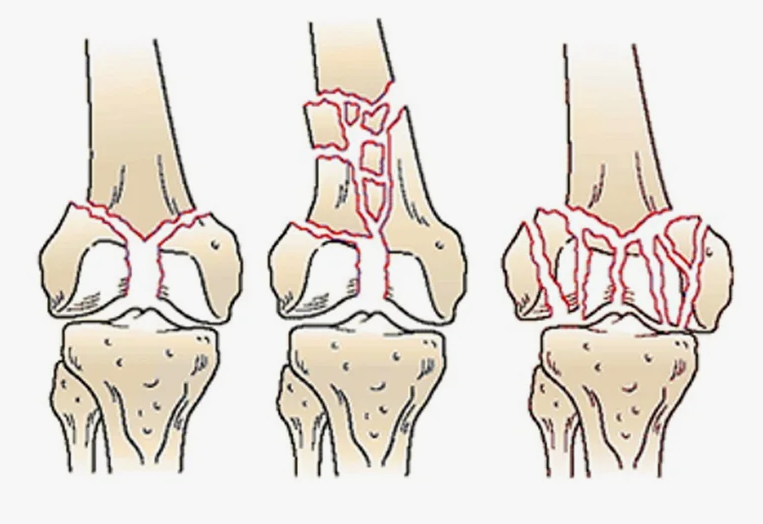

В случае перелома шейки бедра компания МосРентген Центр госпитализирует в Склиф для эндопротезирования.